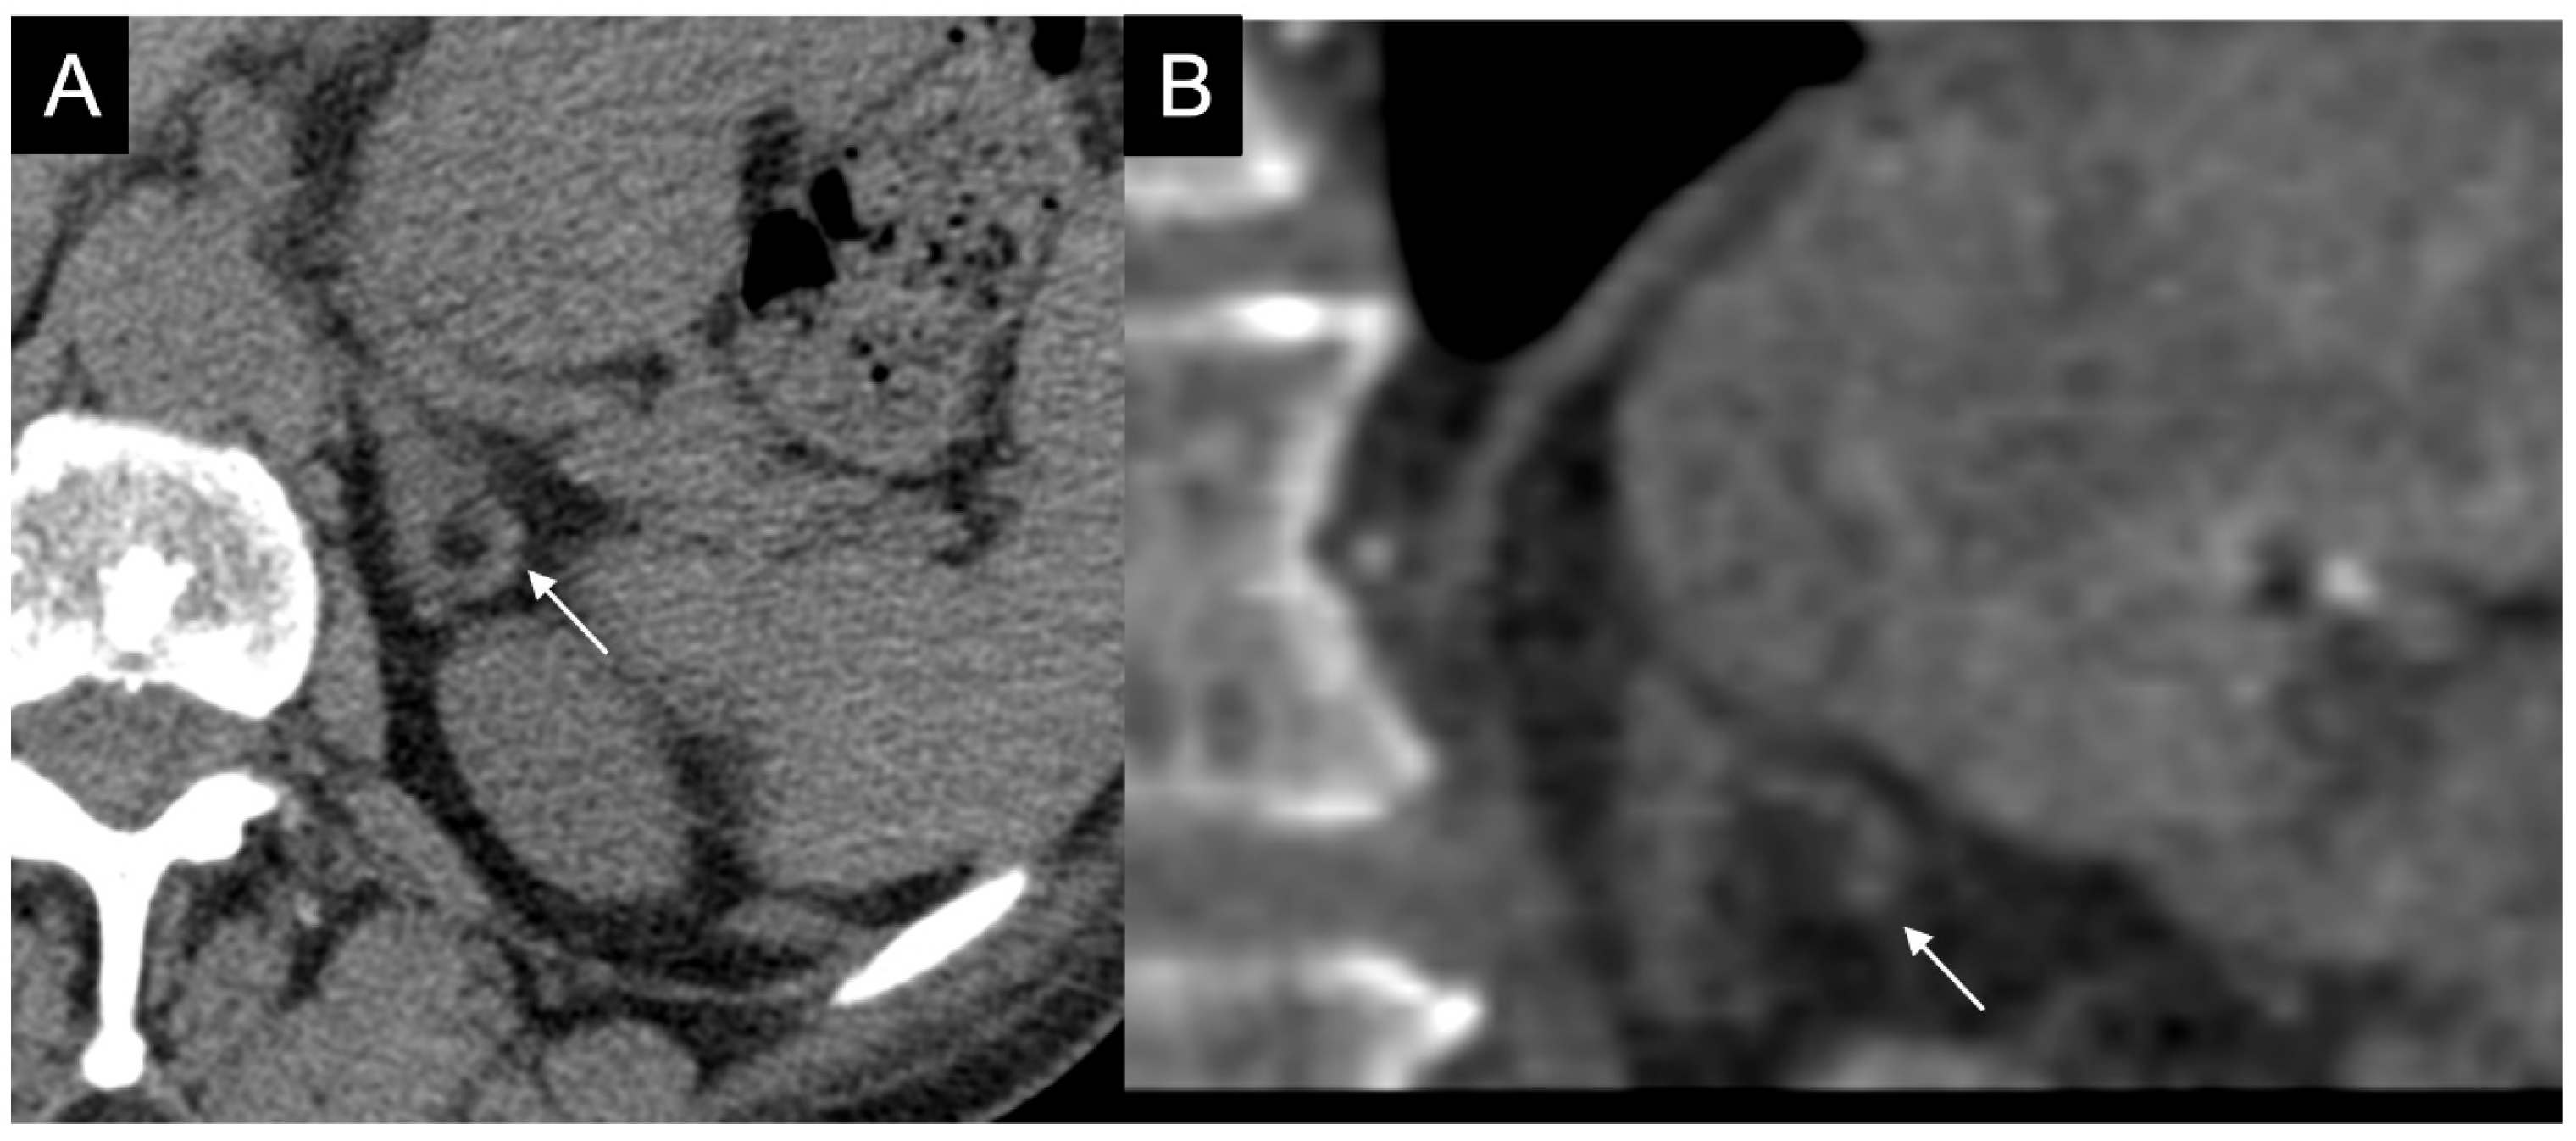

Figure 12.

(a) Unenhanced and (b) venous CT phases show a solid lesion (arrow) in the right adrenal gland with a heterogeneous contrast-enhancement due to necrotic-colliquative phenomena; on histological examination, the lesion was a pheochromocytoma.